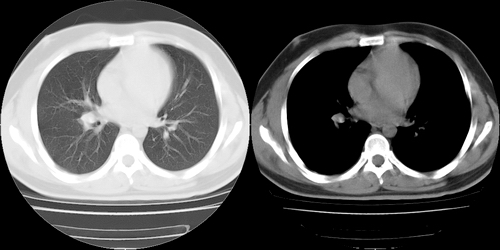

患者 男性 25岁,体检觉得右肺门感觉增大,请会诊,有没有异常?(我科诊断:未见异常)

右肺门增大,气管旁腔静脉后淋巴结肿大

右肺门增大,囊状影与肺动脉分支有关,上叶支气管受压移位。

考虑发生于右肺动脉分支的肺动脉瘤。

鉴别:肺结节病,多侵犯两侧肺门及纵隔淋巴结。

右主支气管及右中叶支气管受压,腔静脉后淋巴结肿大,不知肿块是血管还是淋巴s

没有增强,实在很难说是血管还是淋巴结,纵隔内可见肿大淋巴结,还是先考虑淋巴结吧。我认为

右肺门前方[右侧上叶支气管尖后段分支水平]结节灶,隆突前似有淋巴结显示。结核或肿瘤。建议增强检查

建议增强,右肺上叶前段支气管受压变细,腔静脉后方见肿大淋巴结.考虑结节病或肺门占位.

应该是右肺动脉影,要明确则做个增强扫描。